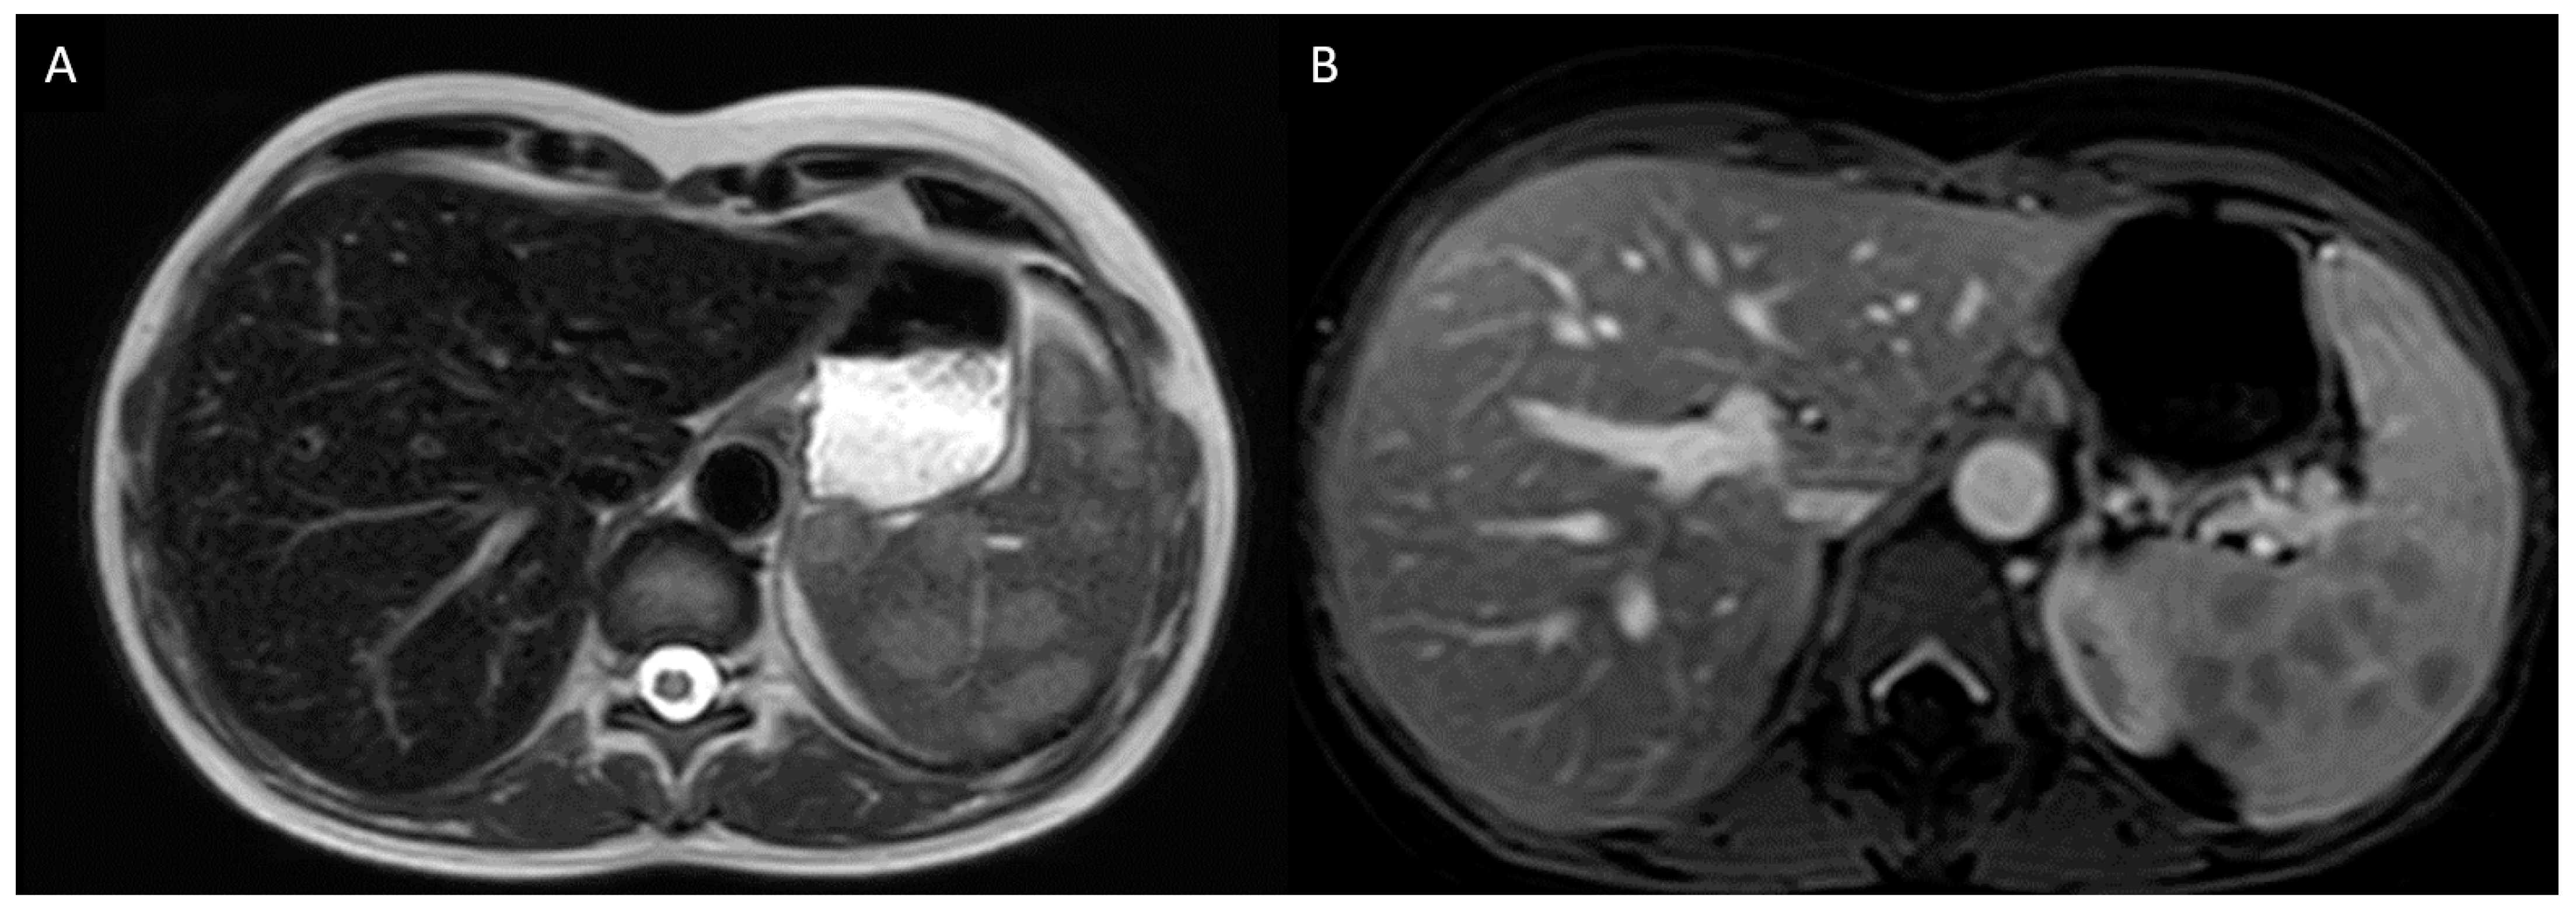

3.7.1. Case Description